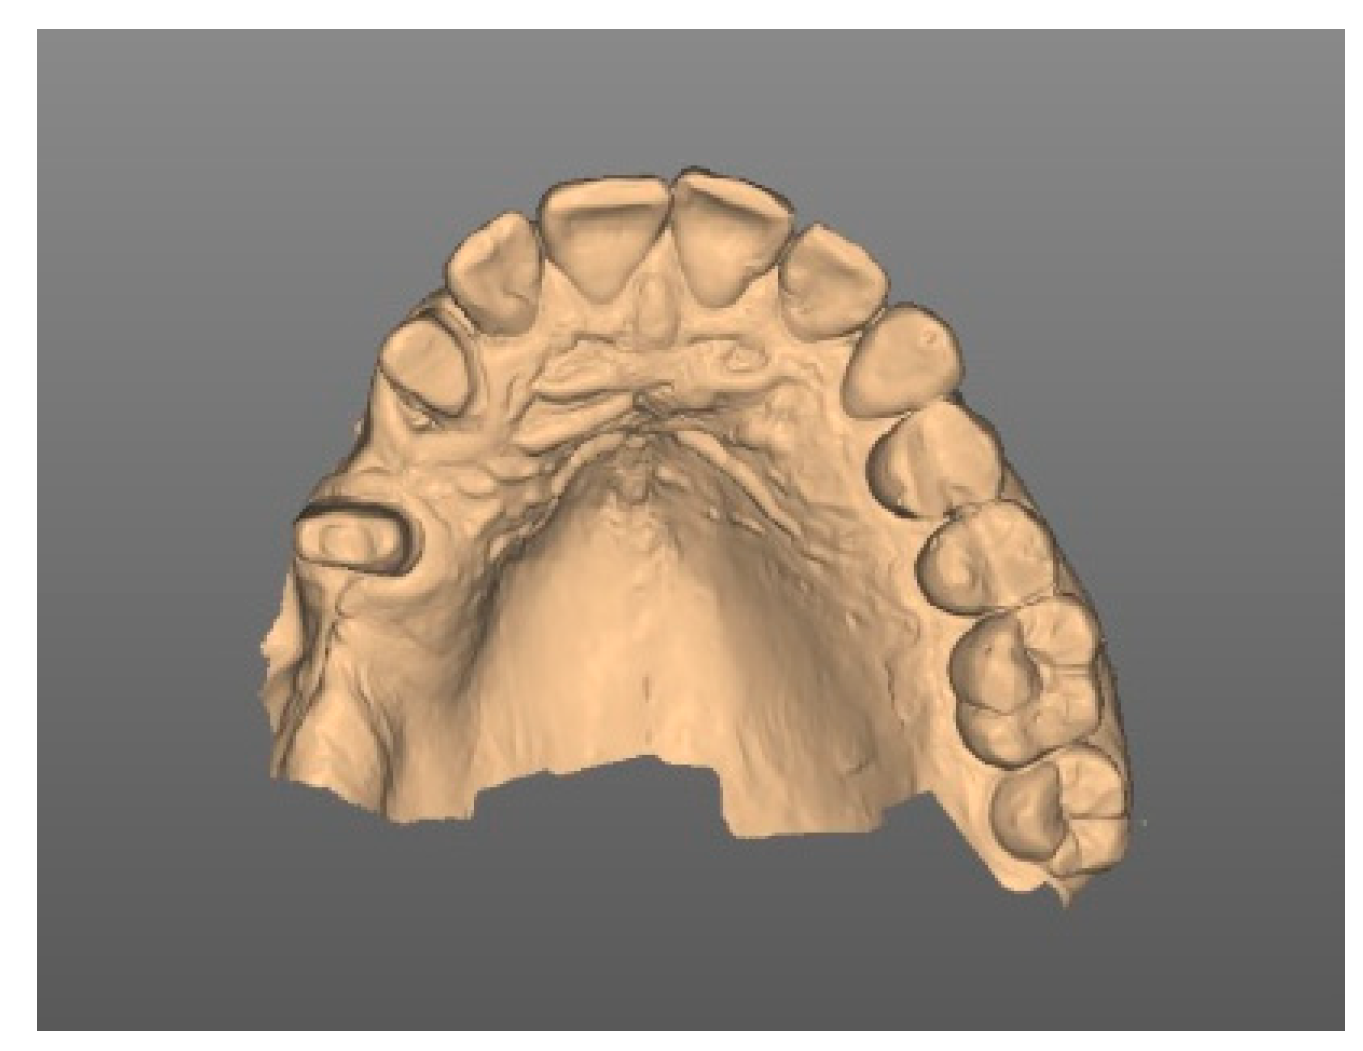

3. Diagnostic and Planning Procedures

| Diagnostic | Intraoral scans |

| Planning | Digital set-up |

| Digital prosthetically driven implant planning | |